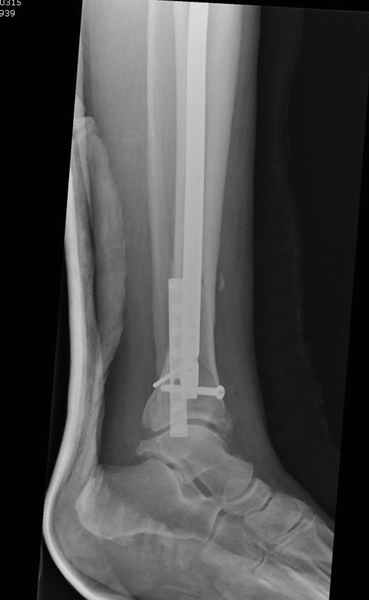

У меня молодой врач на линии, снимки отправил через эл. почту,

спрашивает что делать с больным который поступил недавно, фермер 55 лет падение при пьяной драке в баре, года два назад перенес операцию на лодыжке, на снимках и КТ перелом без вовлечения сустава,

Здесь мы использовали новый Synthes Nail с дополнительными дырками, в проксимальной части 4: по две косых и поперечные (один стандартный а другой динамический), в дистальной части две поперечные, прямая и косая. Вес больного более 120 кг, нагрузку начнем через месяц.

Получилось красиво, поздравляю. Вверху можно было ограничиться одним винтом во фронтальное статическое отверстие, зачем два 45-градусных?

При такий спирали задний край tibia может быть сломан - нет ли этого в данном случае? На всякий случай можно было ввести 1-2 винта 4,5 мм спереди назад мимо гвоздя. Хотя самый дистальный блокирующий винт, возможно, зацепил этот отломок. А какой тут диаметр гвоздя и locking винтов?